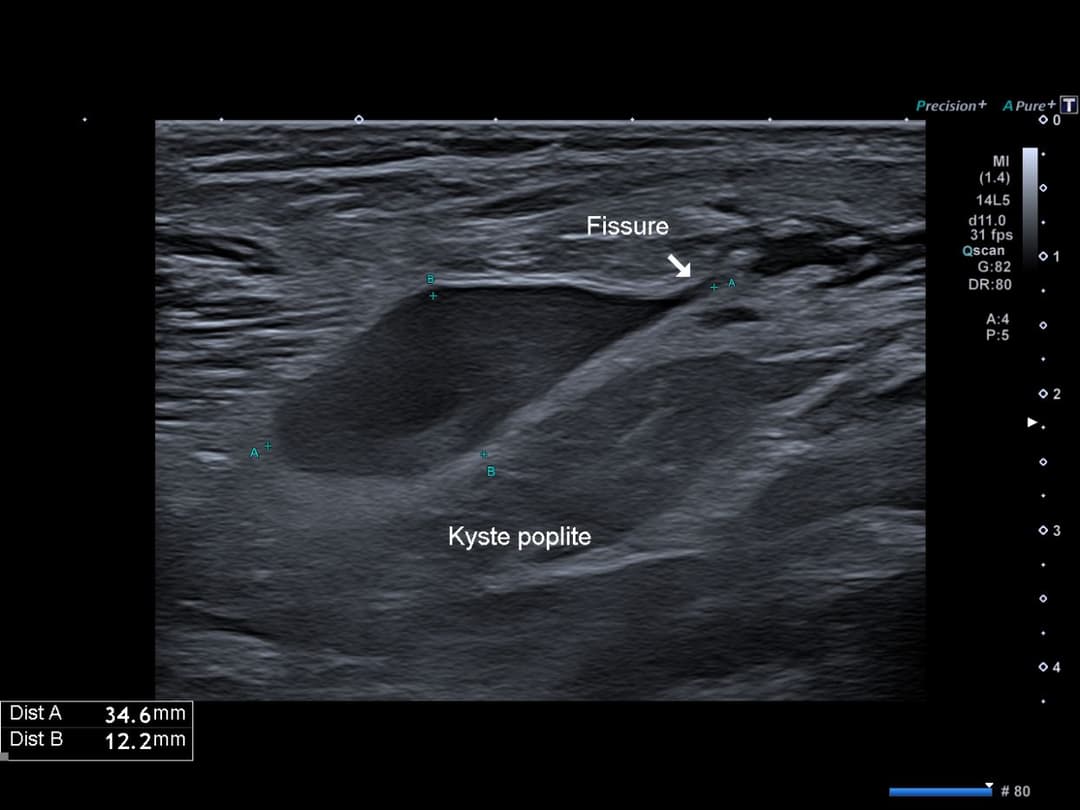

Perte de tension du pôle inférieur du kyste traduisant sa fissuration

Balayage axial cranio-caudal de la zone pathologique